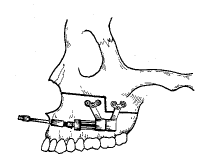

图1 上颌骨牵引成骨示意图(Martin牵引器)

2.上颌骨水平向牵引成骨:腭裂继发上颌骨发育不全3例分别行高位台阶式Le FortⅠ型截骨,使用Martin公司生产的下颌骨水平向牵引器,将其远中固定臂固定于台阶式截骨线上方的颧牙槽嵴处,将其近中臂固定于截骨线下方的磨牙根尖上骨壁(图1)。间隙期5 d,根据术前设计牵引长度每日4次、每次牵引0.25 mm(每日1 mm)分别达到牵引合适长度。观察稳定4个月,Ⅱ期手术拆除牵引器并观察牵引间隙内成骨情况。